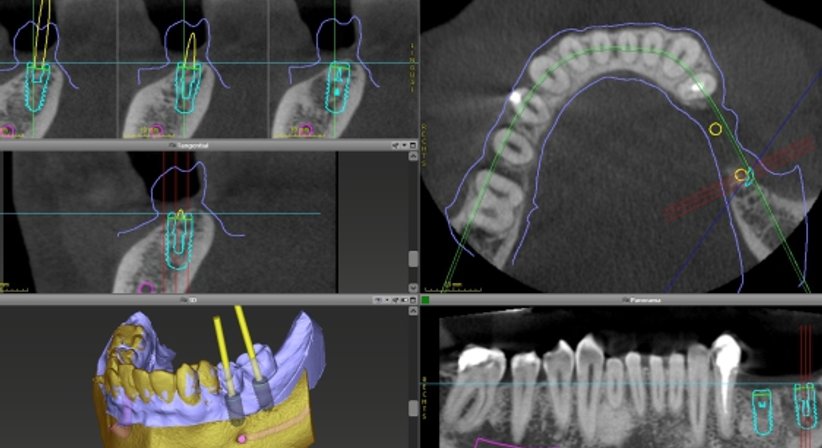

Ich führe die Implantation navigiert bzw. schablonengeführt durcht. Dreidimensionale Röntgendaten (DVT) und eine moderne 3D Planungssoftware mit entsprechendem Übertragungssystem ermöglichen eine exakt vorhersehbare und präzise Setzung des Implantates. Zudem ermöglicht die Software eine genaue Auswertung der vorhandenen Knochensubstanz.

Das Einbringen des Zahnimplantates kann also schon vor Implantatsetzung am Computer in Form eines dreidimensionalen Patientenmodells simuliert werden.

Danach wird die virtuell geplante Implantatposition mithilfe einer computergefertigten, in 3D Druck hergestellten Führungsschablone (Bohrschablone) an die gewünschte Stelle im Kieferknochen übertragen, wodurch das Implantat optimal platziert werden kann.